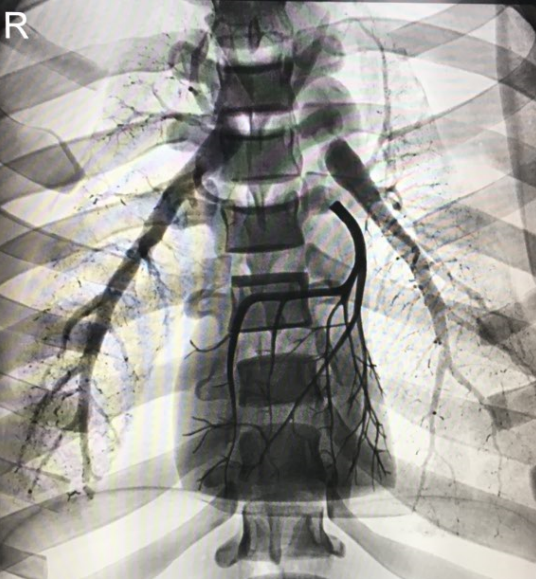

模型尺寸與身高175cm、體重73.5kg男性外部身體相仿,材料為軟組織和骨骼等效材料。

肺部模型處于膨脹狀態(tài)且與胸腔形狀一致。肺動(dòng)脈中注有血液等效材料。

胸肺模型范圍包括頸部到下膈膜,肺部和膈膜可與胸腔外殼分離。

模型中包括左冠狀動(dòng)脈,包含數(shù)個(gè)冠脈不規(guī)則及狹窄模擬區(qū)域。

心肺血管含造影劑的放射攝影胸肺圖像模型

1. 尺寸:與身高175cm,體重73.5kg男性身材相仿